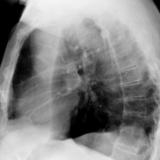

LUL Collapse Case 1 Lateral

Date: 02/19/2004

Views: 3319